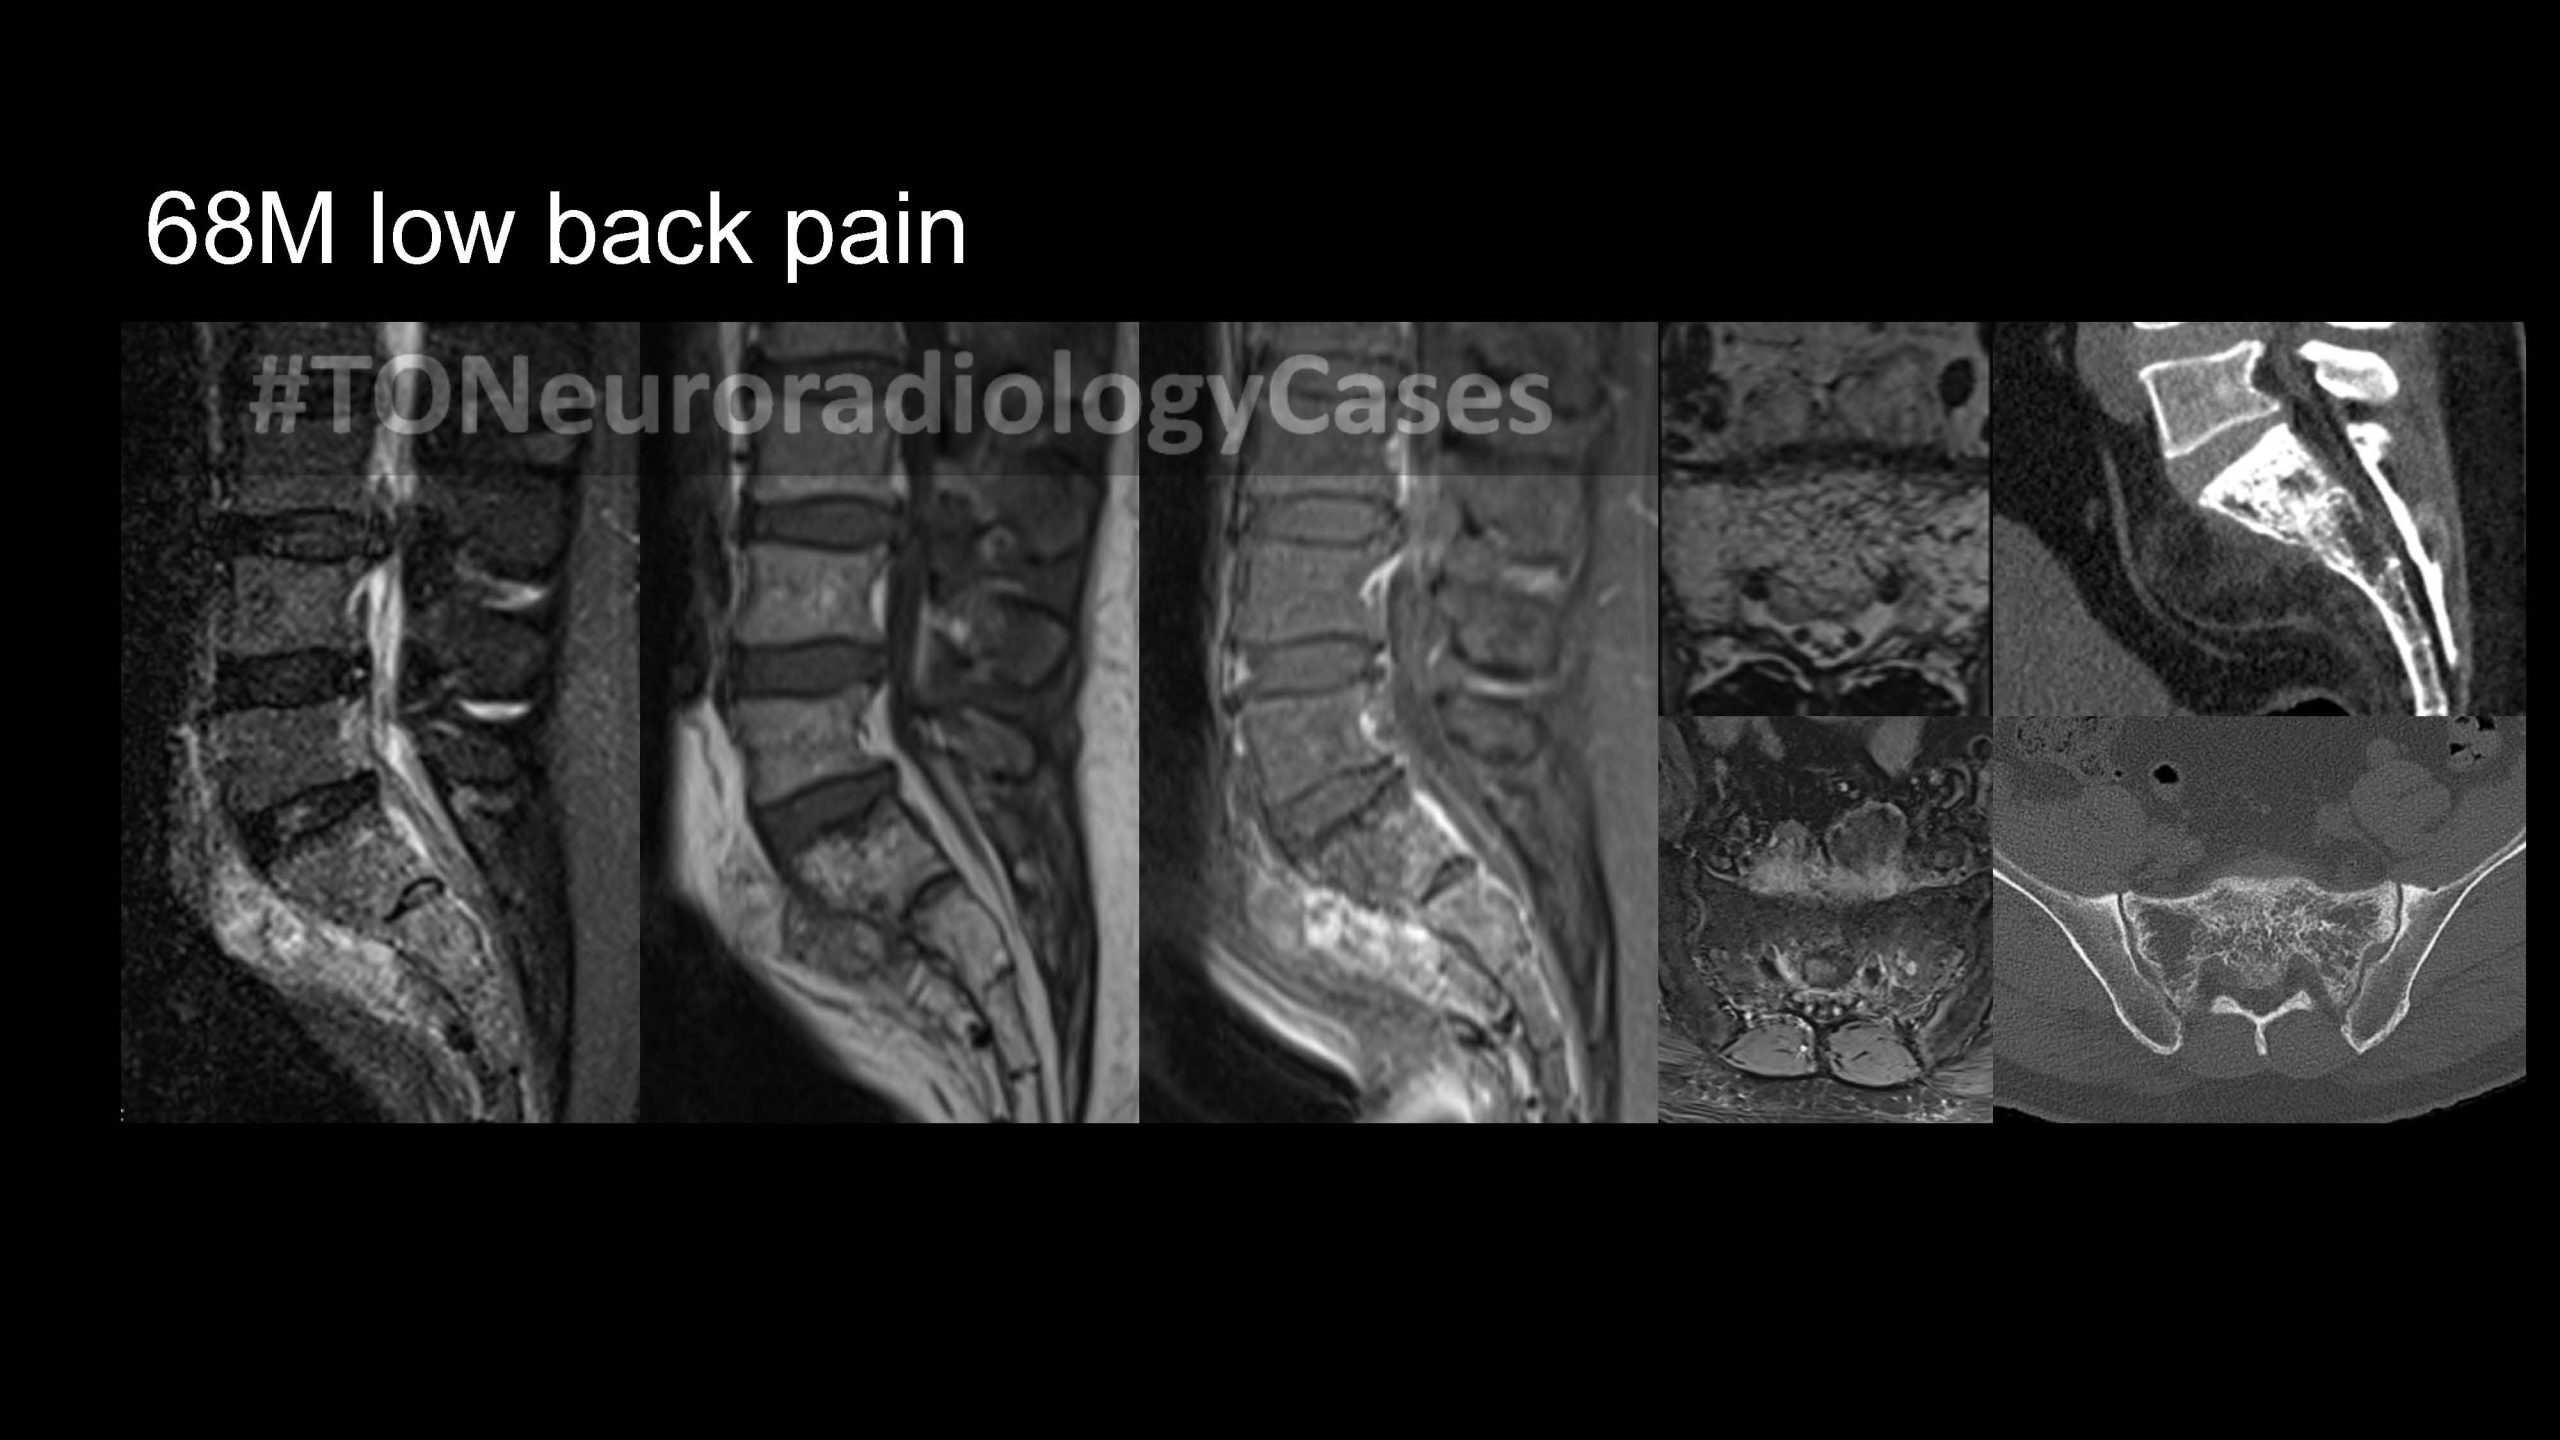

DR. AMY CHEN’S

Neuroradiology Case of the Week

@ Toronto Radiology

Over the past few years, I’ve had the pleasure of curating a “Case of the Week” contest with contributions from radiologists across the city, designed to challenge and engage our neuroradiology fellows at the University of Toronto. This collection showcases a range of neuroradiology cases from our city and have been a fun part of our fellow’s educational experience. I am excited to share this resource with a wider audience, now featured on our Toronto Radiology departmental website.

New cases will be added periodically, so be sure to check back for the latest updates!